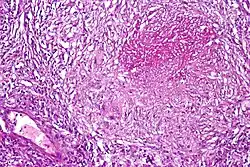

Pulmonary tuberculosis featuring necrotizing granulomas, high power view, H&E stain.

Pulmonary tuberculosis featuring necrotizing granulomas, high power view, H&E stain. -